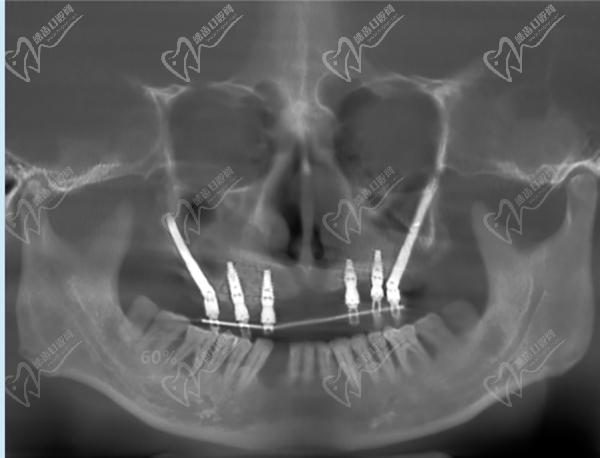

作為廣州市實(shí)力強(qiáng)勁的綜合性口腔醫(yī)院,暨南大學(xué)穗華口腔在種植牙領(lǐng)域名聲在外。醫(yī)院擁有一批經(jīng)驗(yàn)豐 富的種植醫(yī)生,例如馮智強(qiáng)醫(yī)生,并擅長(zhǎng)各種種植牙手術(shù),包括單顆種植、多顆種植、微創(chuàng)種植、數(shù)字化種植、半口/全口種植,甚至難度技術(shù)高的穿顴穿翼種植。

半口種植牙·集采種牙:21860元起

全口種植牙·集采:42720元起